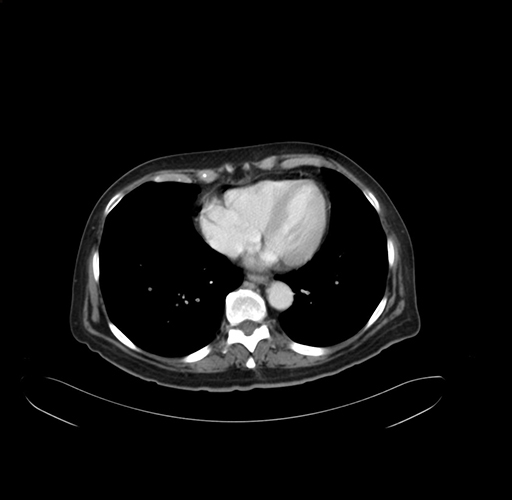

Pre-Chemo: Axial Venous

Axial Venous